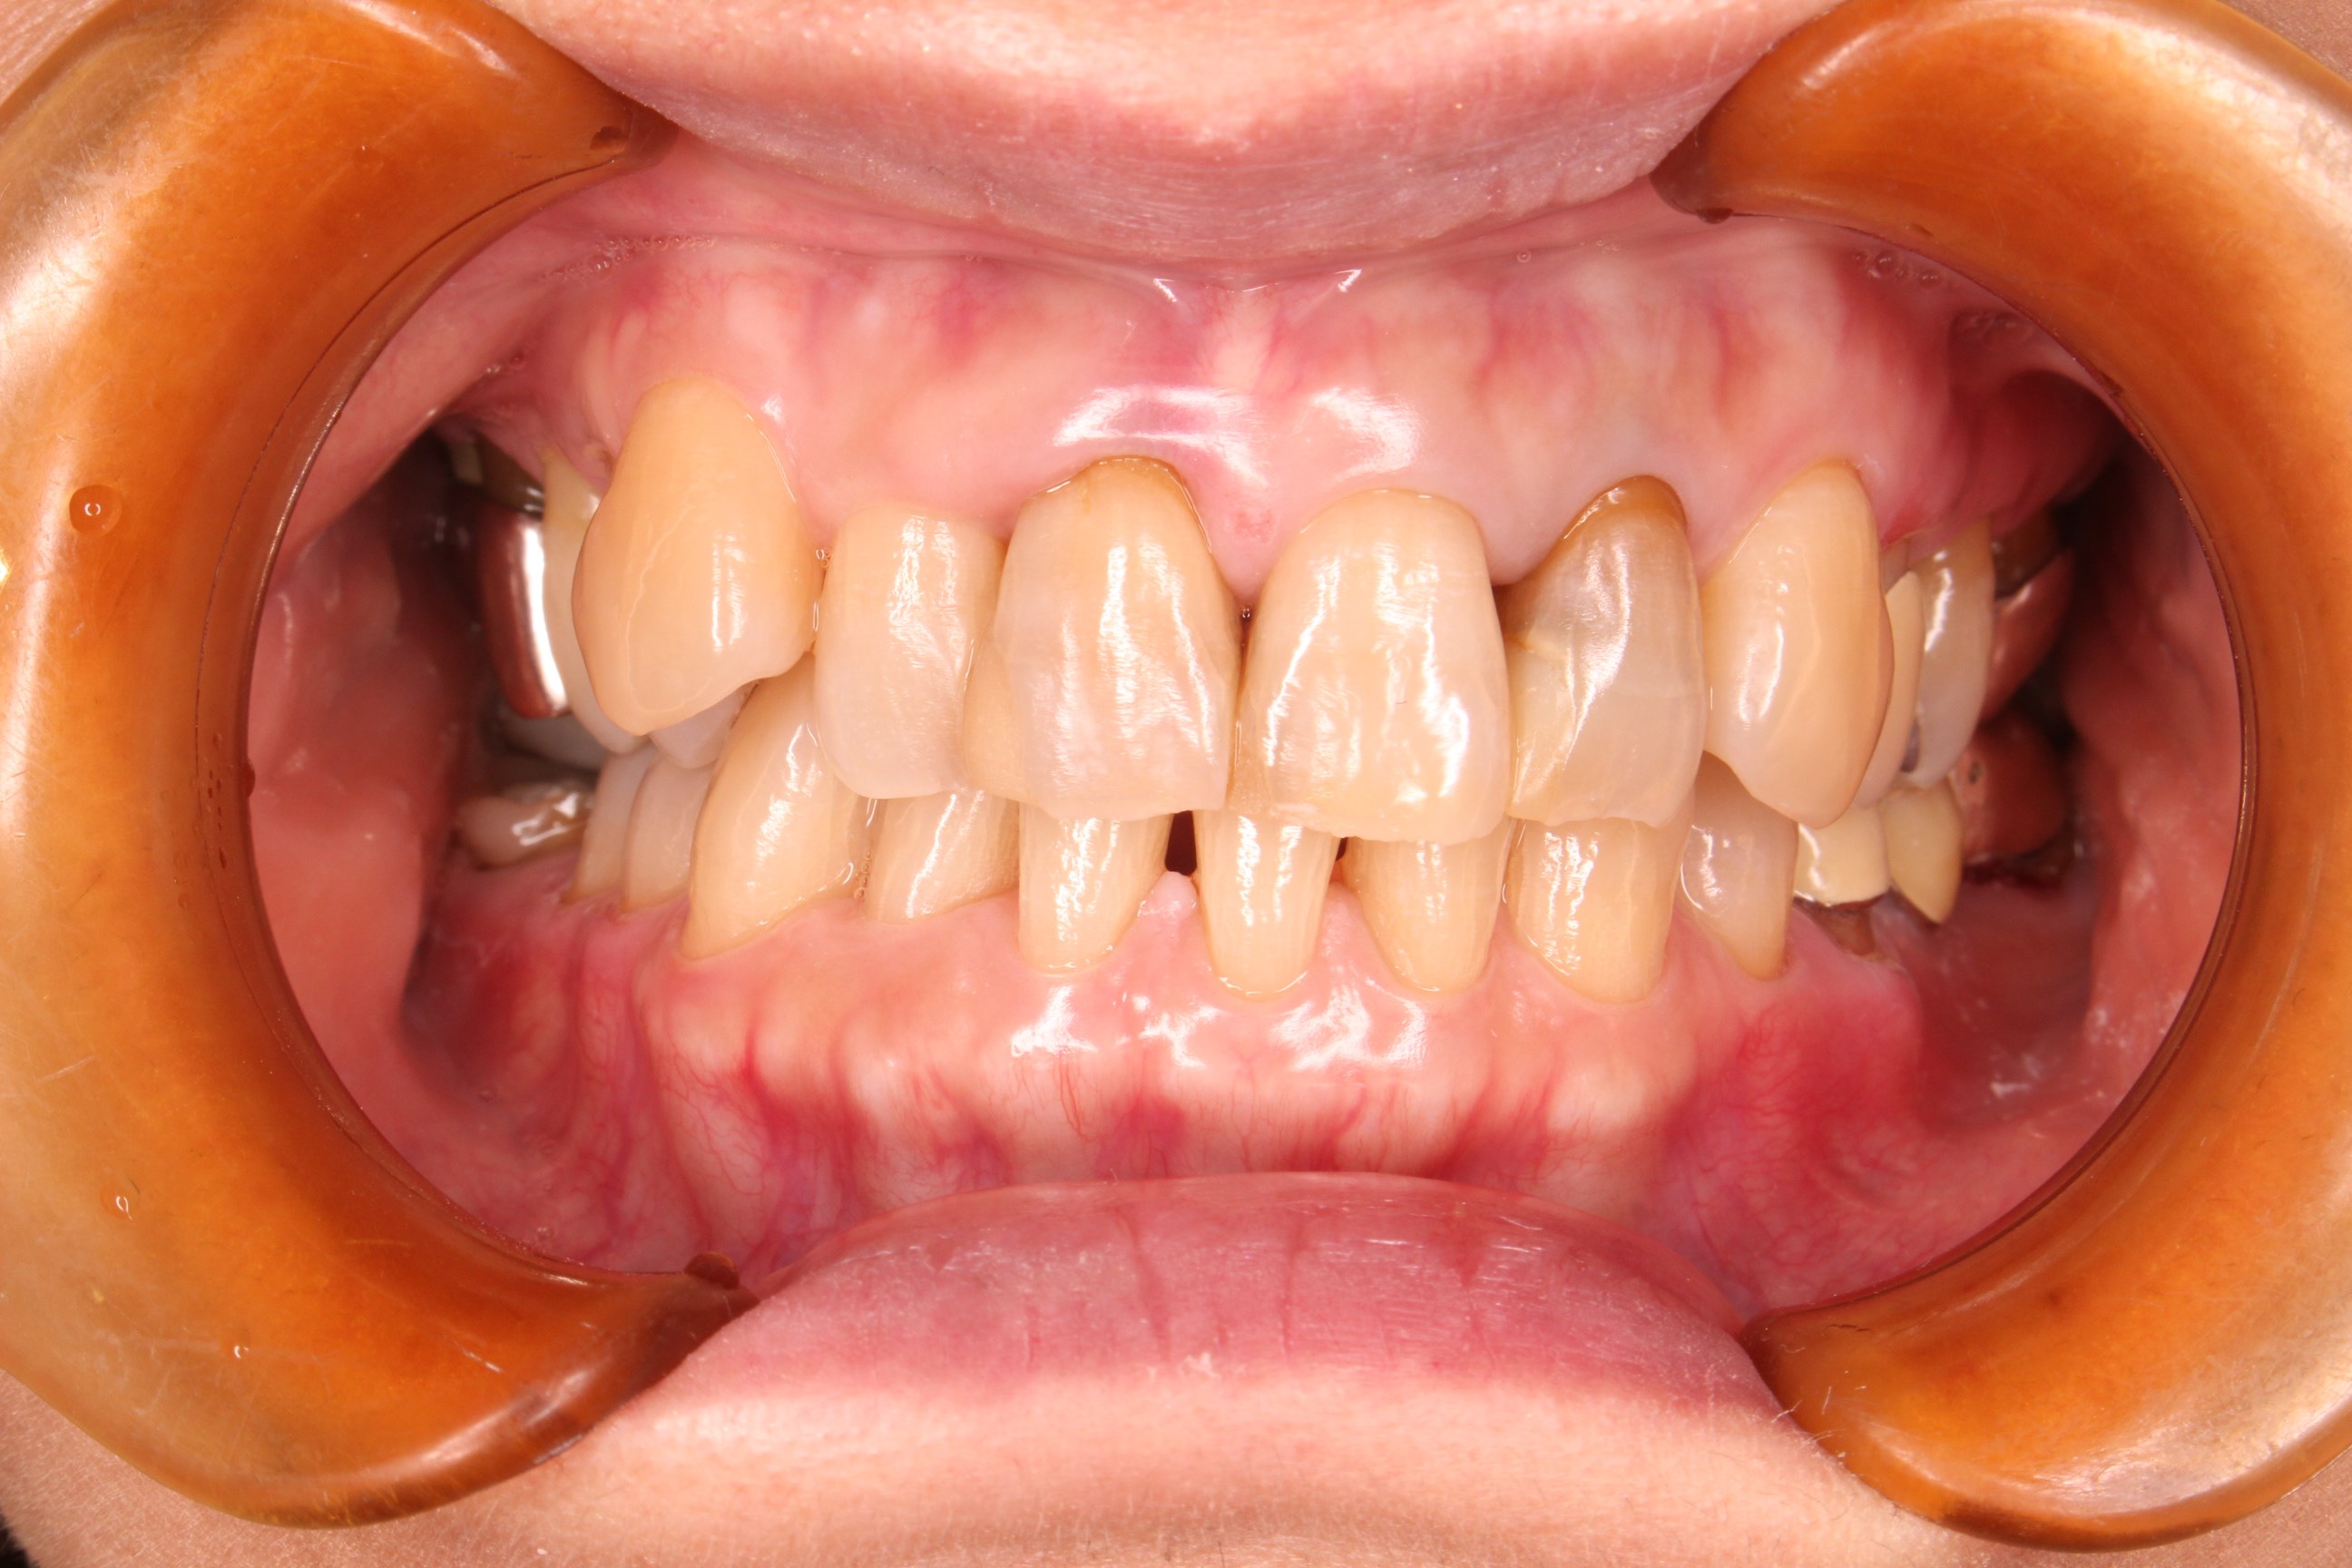

(初診時)

長年、他院で虫歯と歯周病の治療を繰り返していらっしゃいました。

治っている実感がなく、治療を繰り返すことを辞めたいとのことで来院されました。